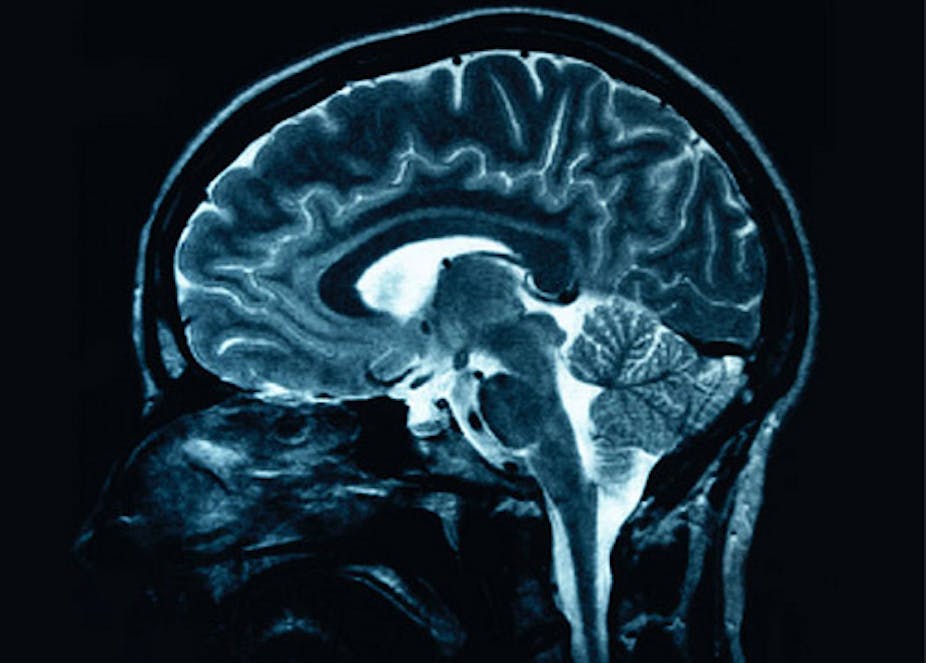

There are numerous brain imaging techniques that allow us to see the activity of the brain, these include Positron Emission Tomography (PET) and functional Magnetic Resonance Imaging (fMRI).

These techniques have revealed that all parts of the brain show some level of activity, except in the case of serious damage.

The figure below is an individual PET scan at rest. We don’t see any black areas (which would indicate inactivity), so the entire brain is showing some level of activity.